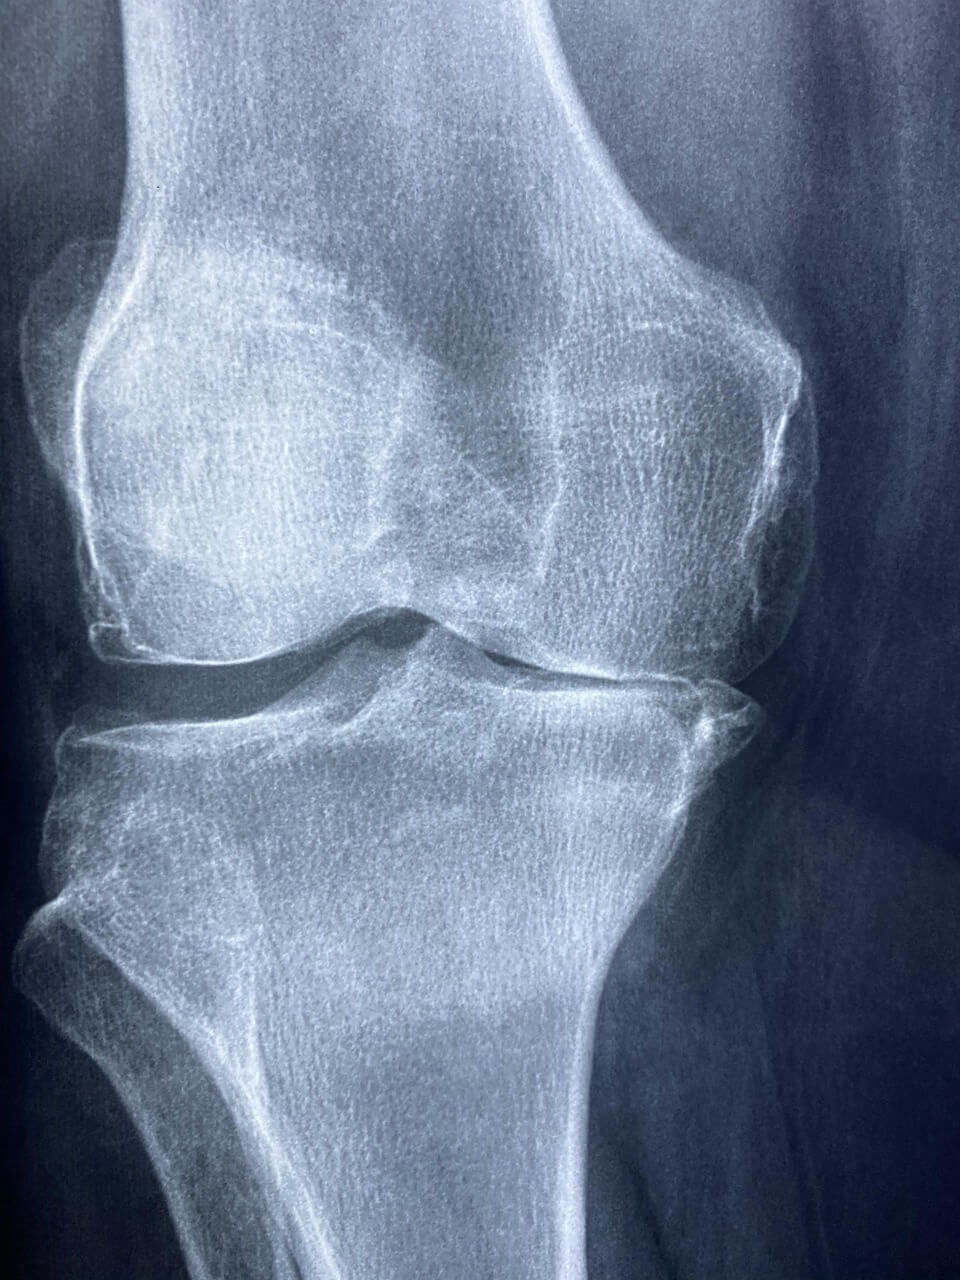

4-2. 영상 검사 (X-ray, MRI)

X-ray 검사에서는 관절 간격이 줄어든 것을 확인할 수 있으며, 진행된 경우 뼈의 변형도 나타납니다. MRI 검사는 연골 손상 정도를 더 세밀하게 파악할 수 있어 조기 진단에 도움이 됩니다. 이러한 검사는 관절염의 진행 정도를 정확히 알 수 있는 중요한 도구이므로 주기적인 검사를 권장합니다.